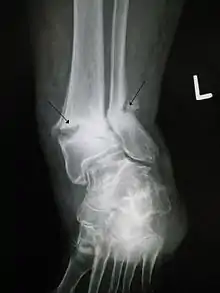

![]() | |

| Internal and external views of an arm with a compound fracture, both before and after surgery | |